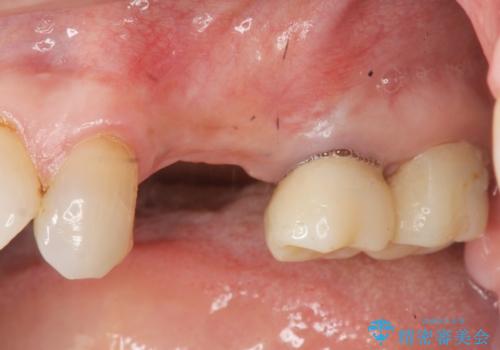

- グラグラする小臼歯の治療、全体的な治療のやりかえを希望され来院されました。

歯の穿孔(内部穴が開いている状態)破折等、歯を保存することができない問題が小臼歯には認められたので抜去を行います。

抜去後の補綴治療は長いブリッジではなくインプラント治療を希望されましたが、穿孔・破折による周囲の骨吸収をリカバリーすべく骨の造成を伴うインプラント治療を計画します。